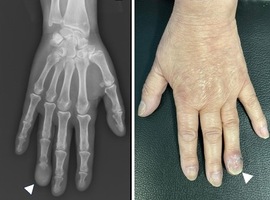

Acral Metastasis of Oral Squamous Cell Carcinoma: A Rare Presentation

Volume 8, Issue 1

:

Read More